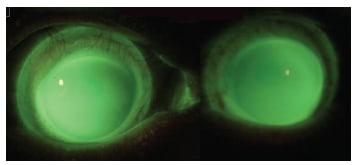

The distance visual acuity with these lenses was 20/20 OD and OS and 20/15 OU. Slit lamp examination showed that both lenses exhibited optimal central and limbal clearance with no impingement (Figure 6).Three months later, we found no change in fitting relationship, vision, or comfort, and the patient was very satisfied with these lenses.

Figure 6. Final lens-to-cornea fitting relationship OD (on left) and OS (on right) in Case 2.